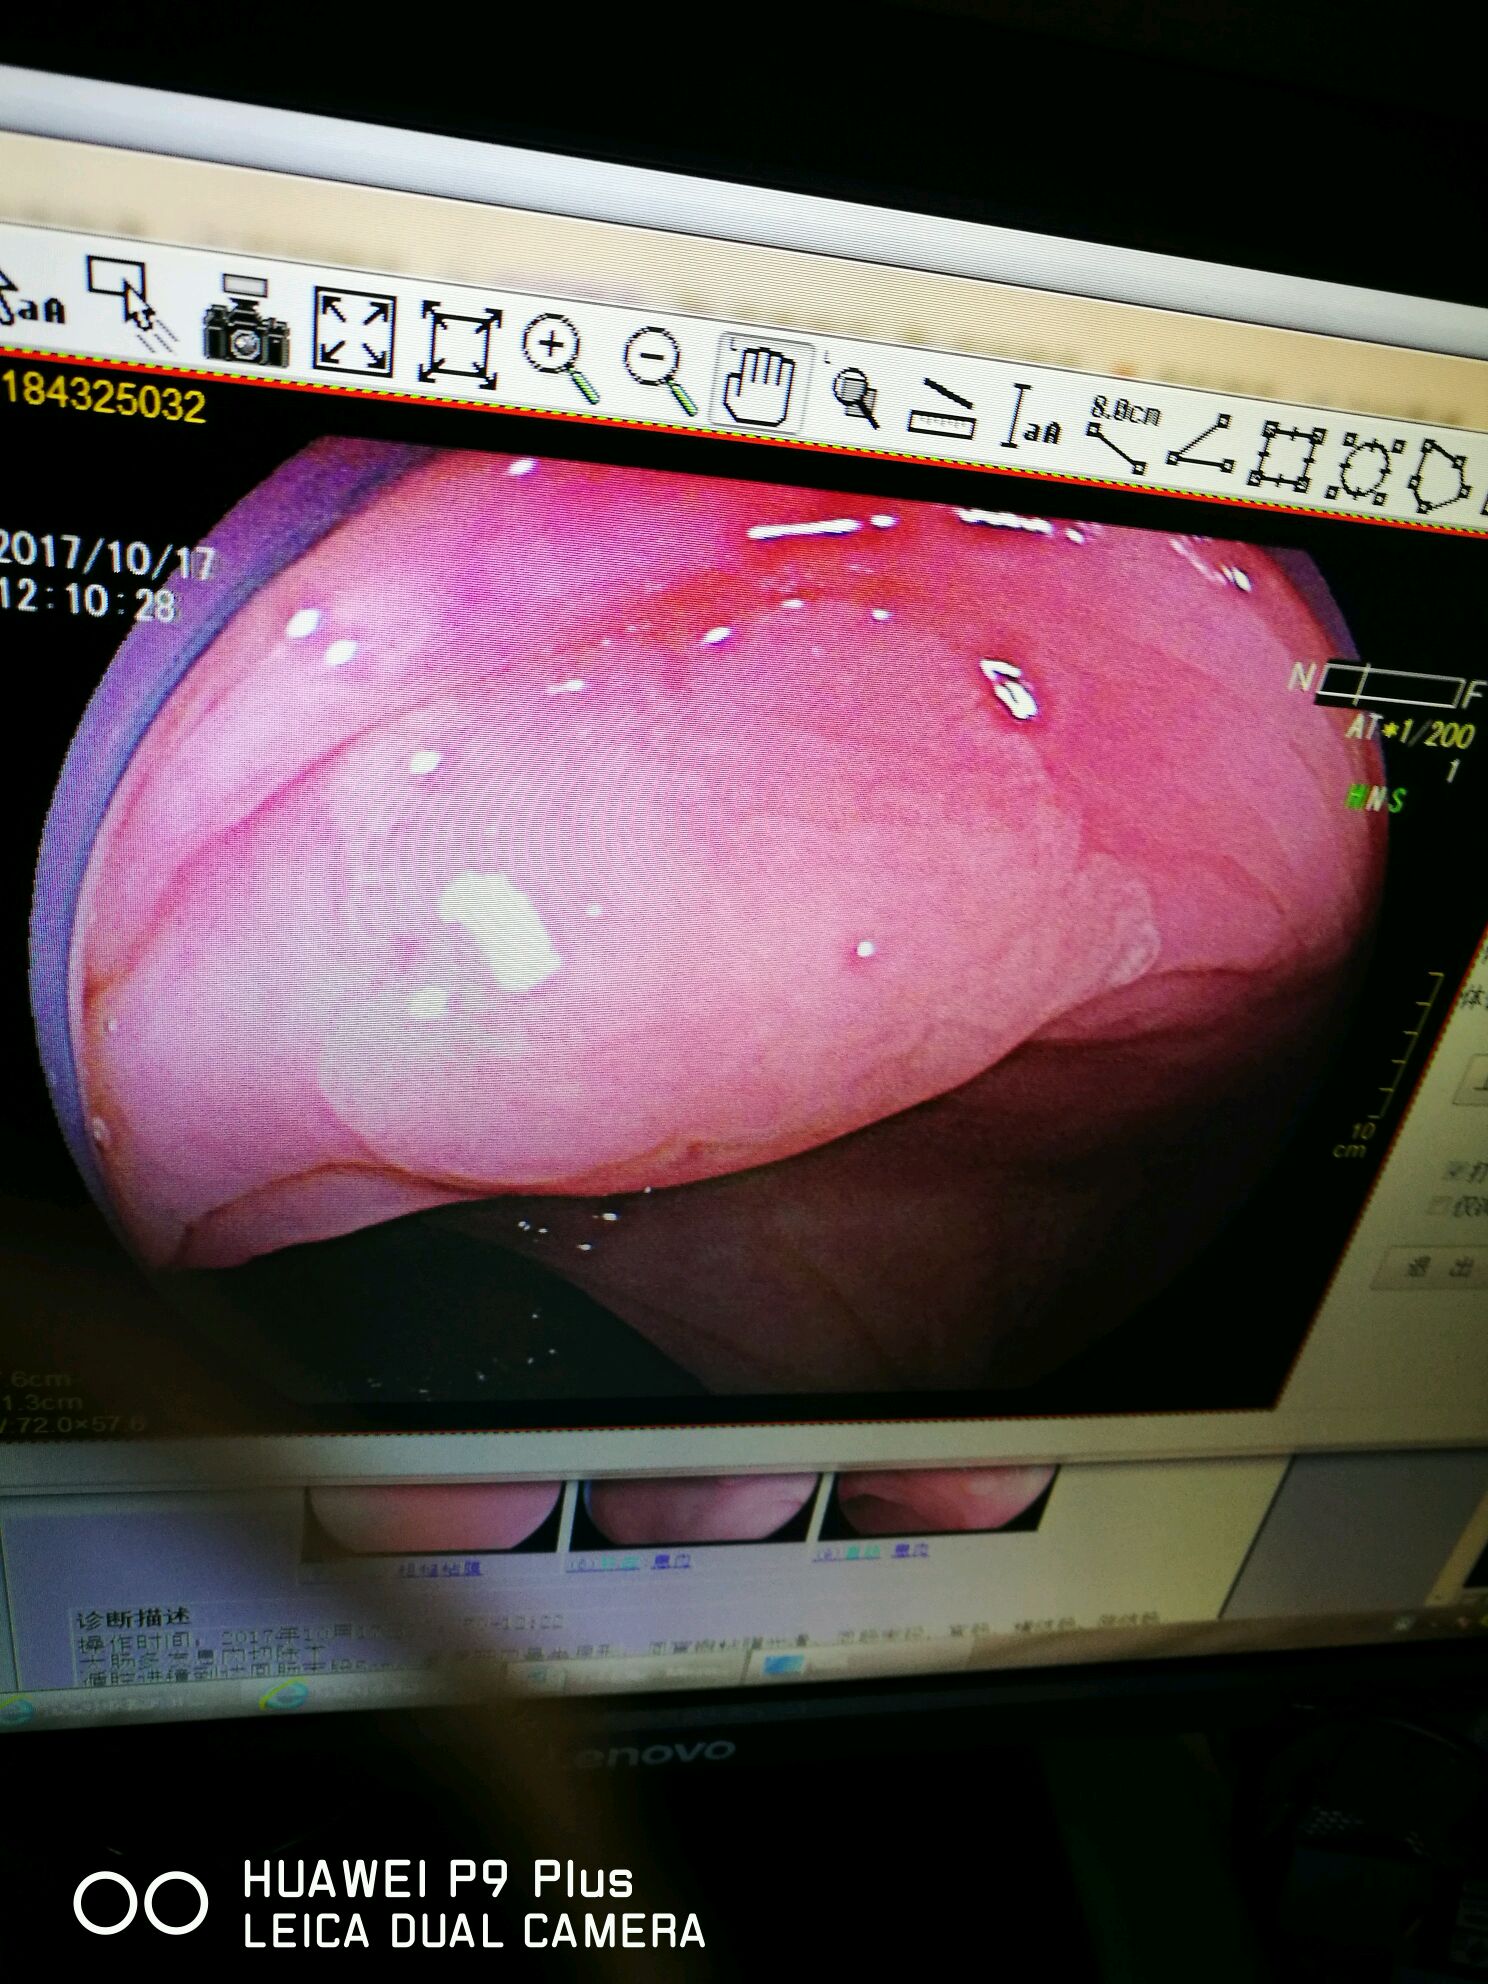

图片发自160医生App